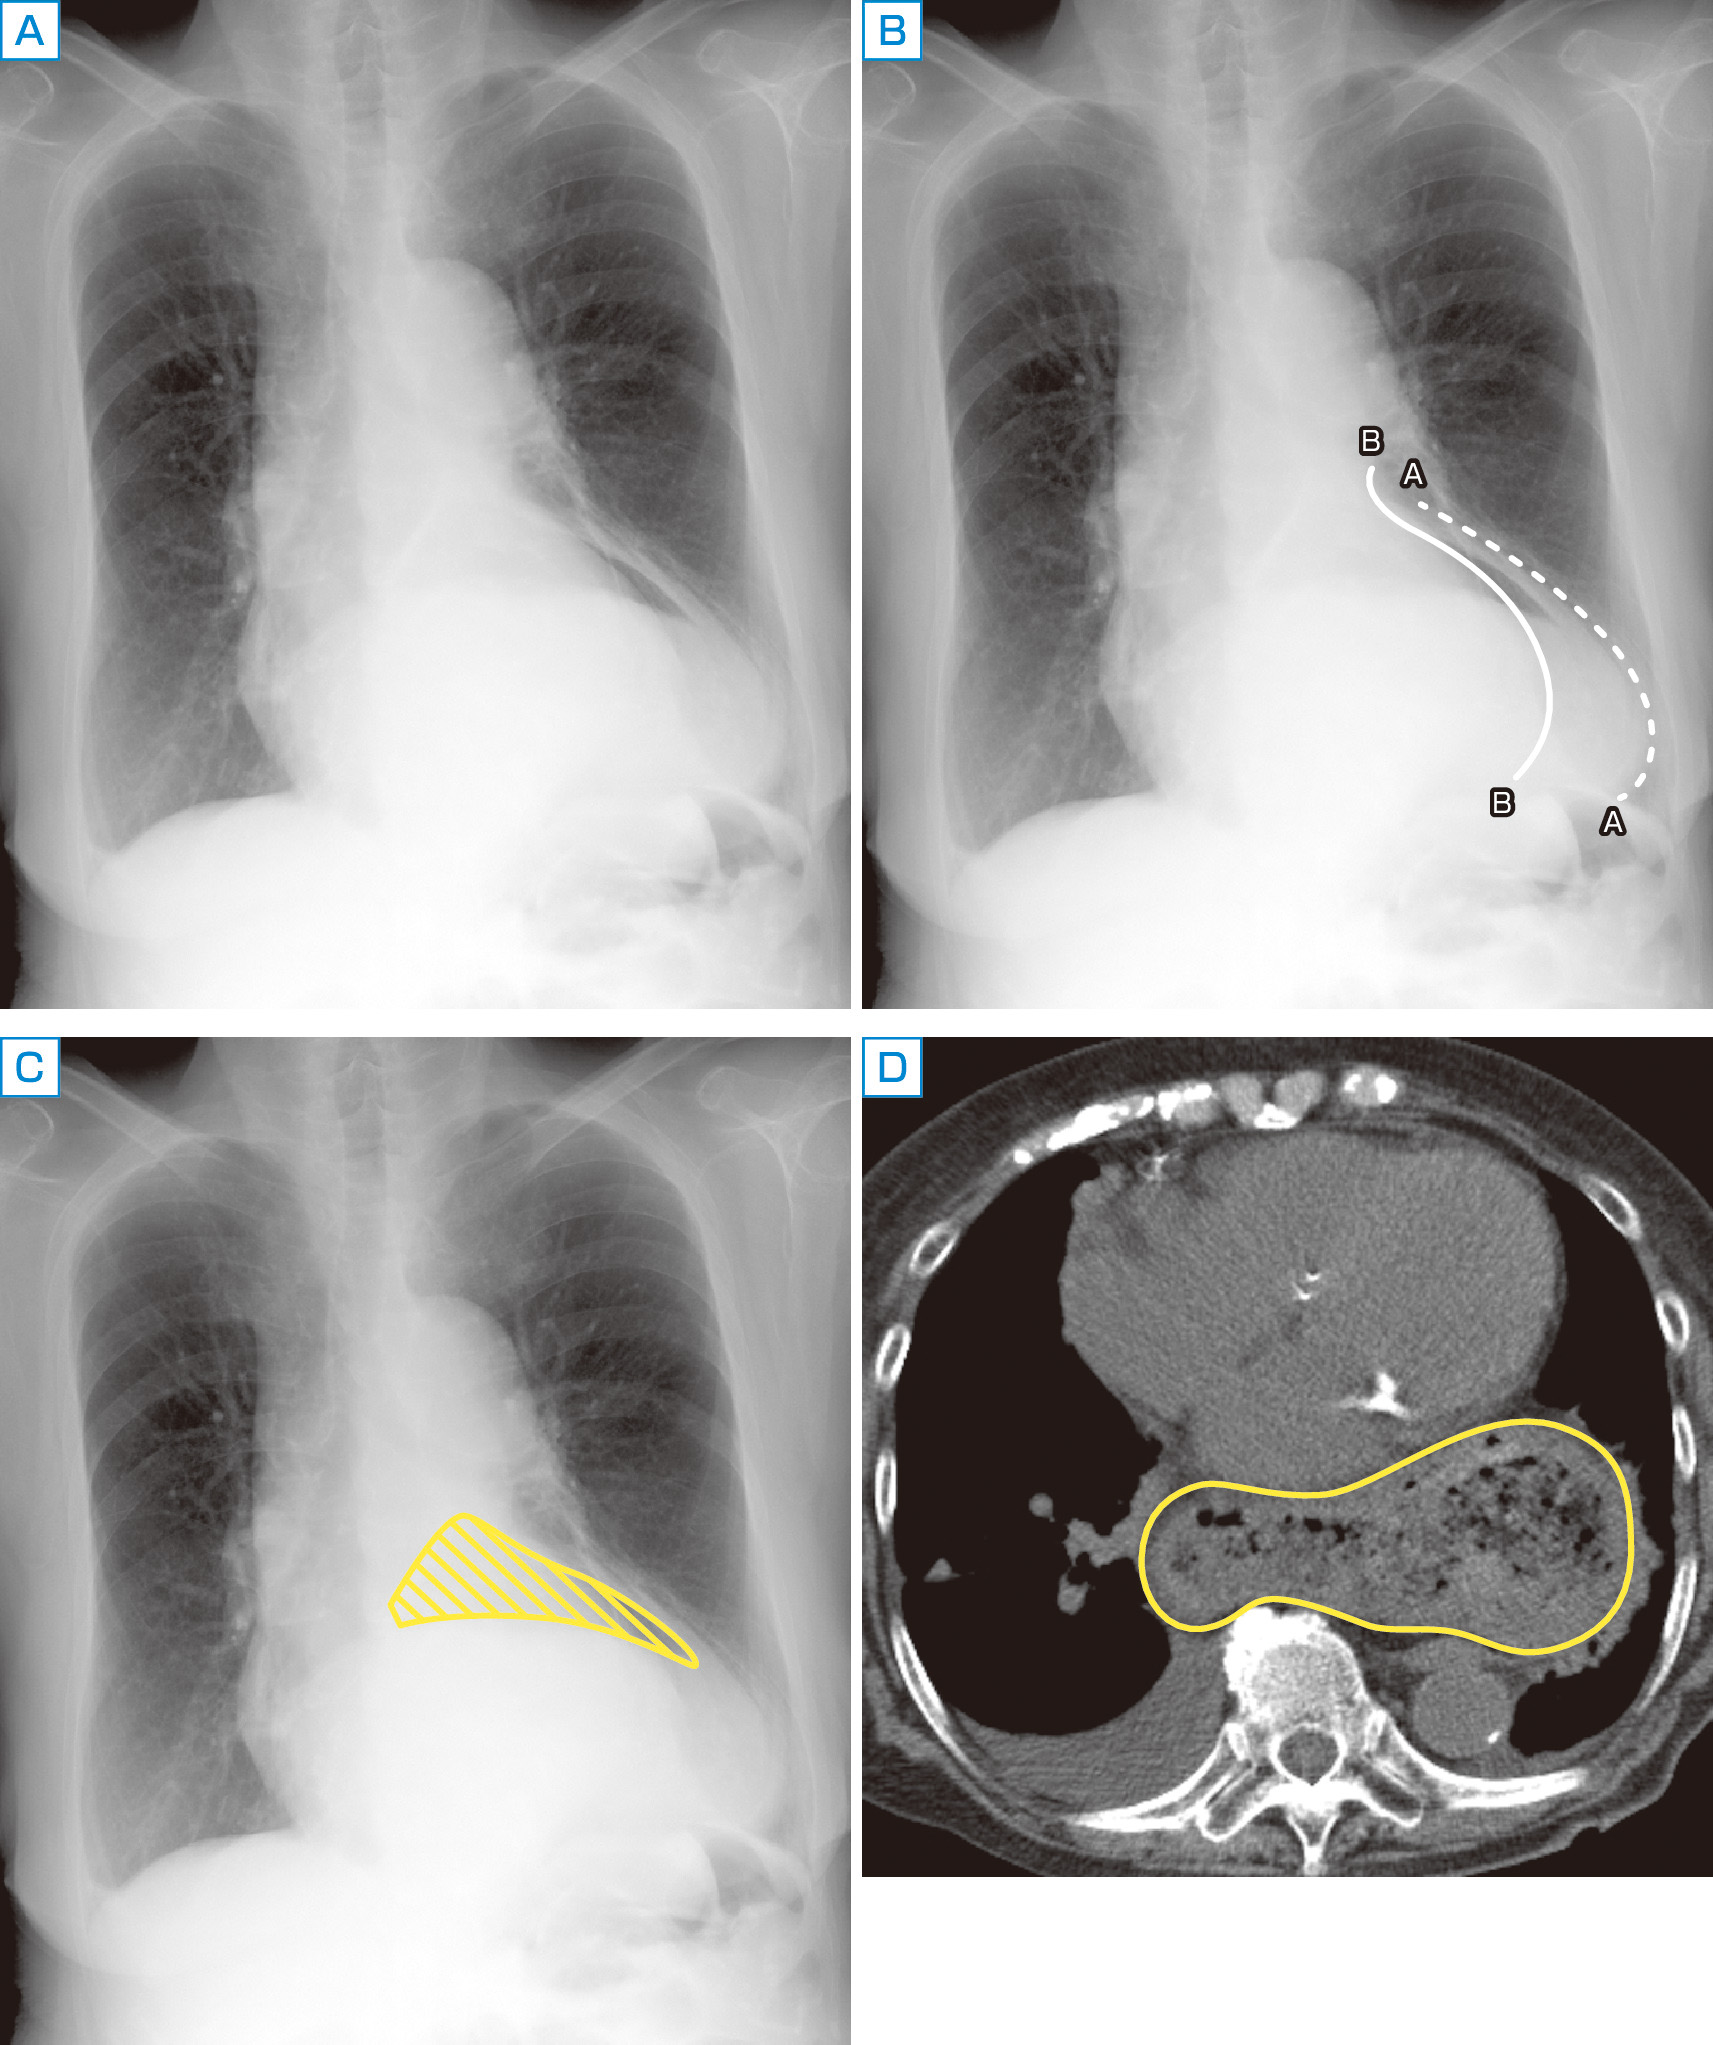

心拡大や大動脈の蛇行が認められるが,その他に気になる所見はないだろうか (A).心左縁を図Bの破線Aと判断した方はおられないだろうか.実は心左縁は線Bである (ただし下部は不明瞭).では破線Aは何の陰影なのであろうか.本症例ではCの斜線で示された空気濃度領域に注目していただきたい.他の目的で撮影された胸部CTにて胃のほぼ全体が縦隔に脱出する傍食道型の食道裂孔ヘルニアがみとめられており,Cで示されている空気濃度の領域は胃内のガスと考えられる.DのCT横断像で囲った部分が食道裂孔ヘルニアを起こした胃であり,内部に食物残渣が貯留している.本症例のほど大きなヘルニアはまれではあるが,高齢女性などで食道裂孔ヘルニアの陰影が心大血管影に重なる腫瘤影として認められることはしばしばある.縦隔の腫瘤様の陰影内にガス像や液面をみとめた場合は,食道裂孔ヘルニアの可能性を考えたい.